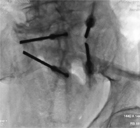

Mme P., 80 ans, ostéoporotique, présente 3 fractures vertébrales.

Elle a récemment chuté et a présenté une impotence fonctionnelle et de violentes douleurs fessières. La scintigraphie a permis facilement de conclure à une fracture du sacrum.

Devant l’importance de l’impotence et afin de réduire la période d’handicap, il a été décidé de cimenter. Mme P. a pu se relever le lendemain.

Ci-dessous les radios.